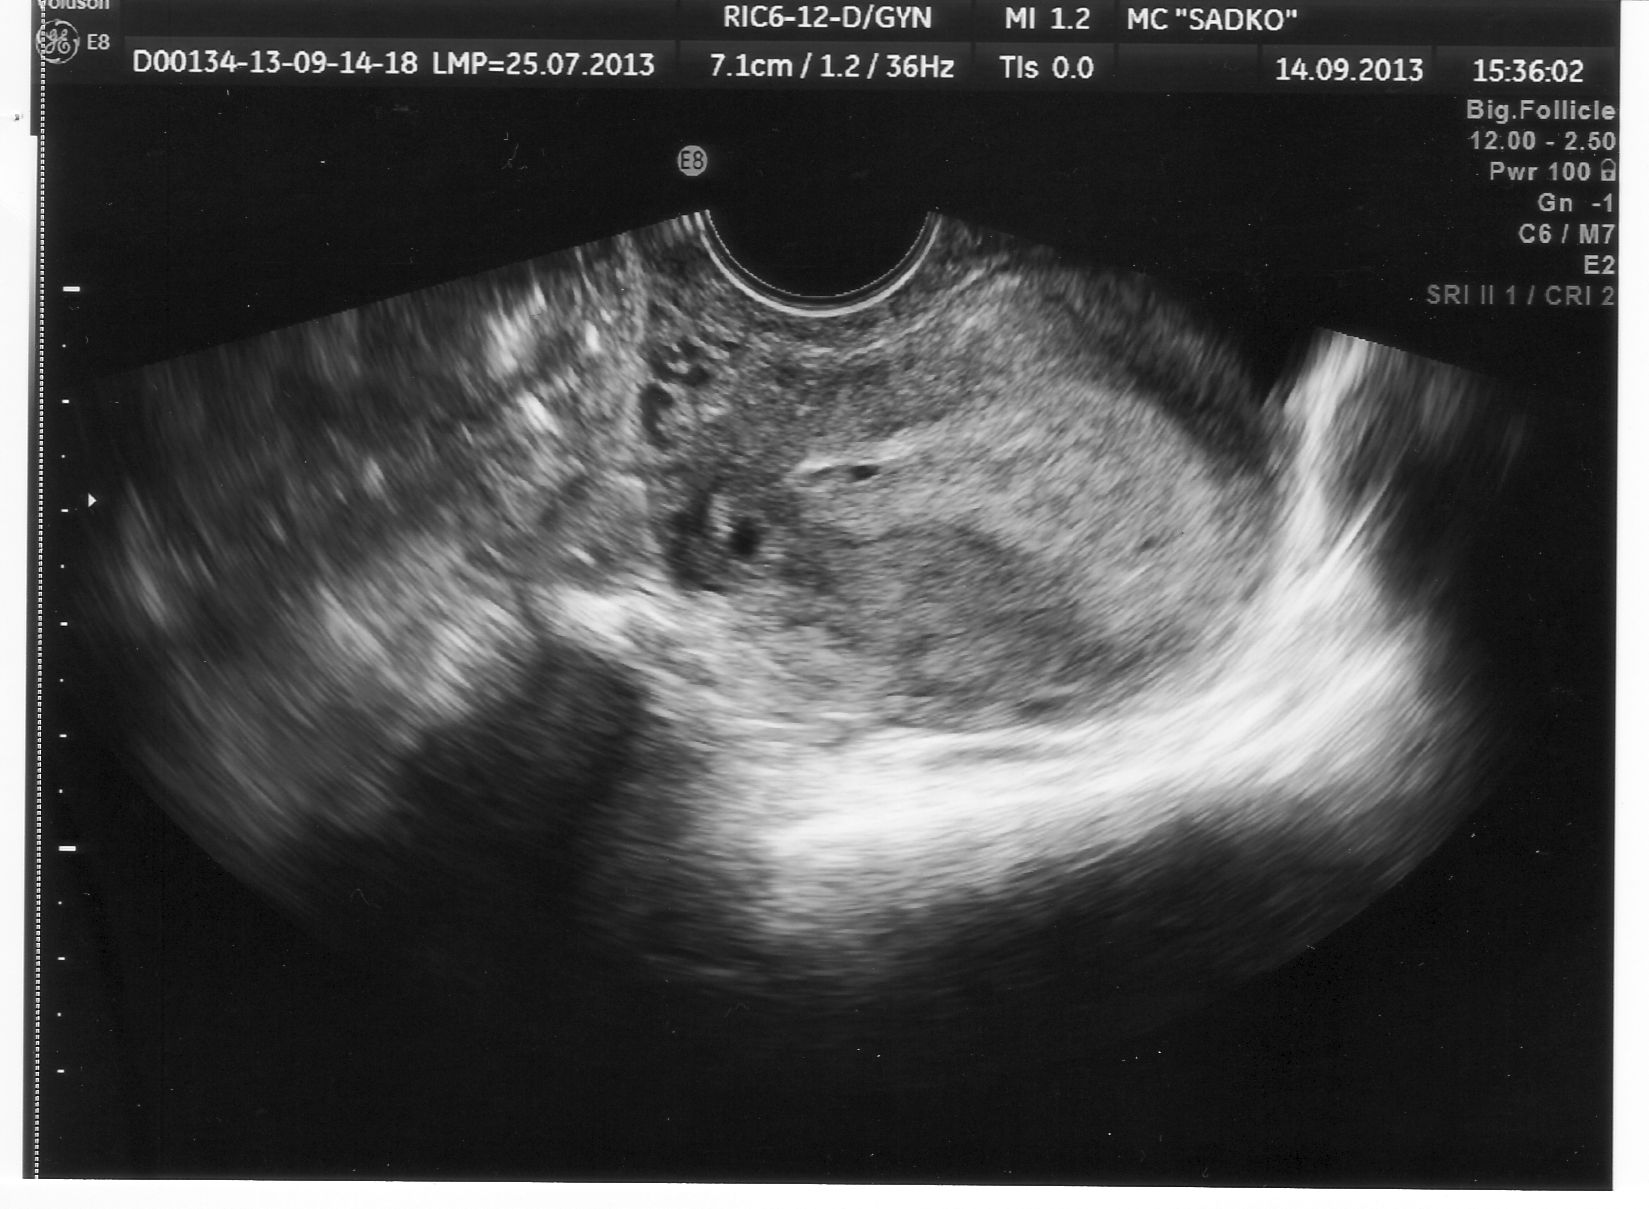

Диагностика беременности на ранних сроках: методы и технологии